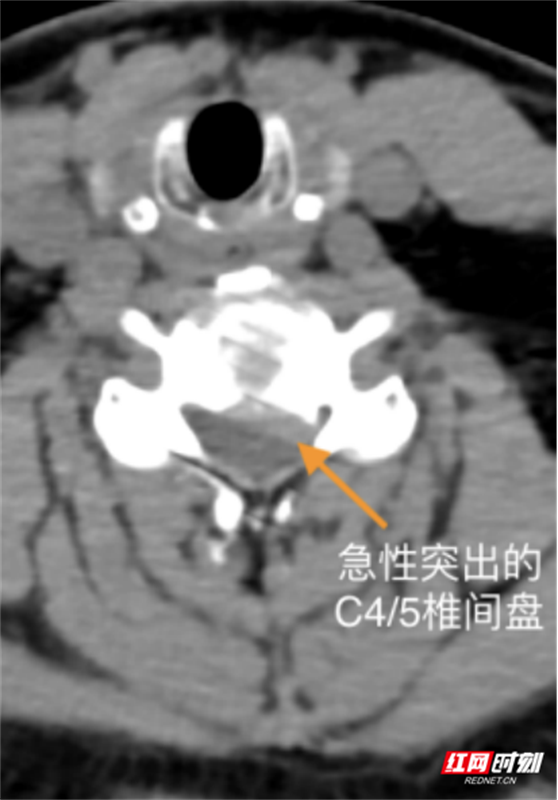

随后,患者相继出现头晕、头痛、呕吐及会阴区麻木。医疗团队紧急启动预案,查CT与MRI结果排除脑出血与急性脑梗死,最终确诊为颈3/4、颈4/5椎间盘突出压迫脊髓,伴脊髓部分变性,解除脊髓压迫为治疗关键。